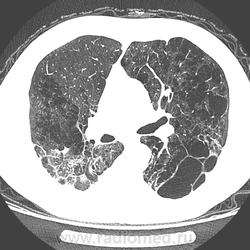

Уважаемые коллеги, как вам такая эмфизема? Как бы вы патоморфологически классифицировали её?

Вообще, как показывает практика, многие клиницисты не понимают разницы в кистах легких, буллах, пузырьках, бронхоэктазах ну и, конечно же, в видах эмфиземы. Подискутируем?

Мне кажется, что здесь есть и кисты. и буллы, и бронхоэктазии, и участки кистозного фиброза, глубоко порочная паренхима, наверно врожденноготхарактера?

Буллезная. А клиницистам, действительно все равно. Но уж точно не все равно для них - объем поражения.

Буллой, насколько я знаю, называется участок эмфиземы диаметром более 2 см. Бронхоэктазов я здесь не вижу. А "киста" - это несколько неопределенное понятие, собирательное. В принципе, любую тонкостенную воздушную полость в легком можно назвать кистой.

Присоединюсь. В верхних отд. только буллы, а средн. и нижних отделах и всё остальное.

Сергей Николаевич, в первом наблюдении присутствует эмфизема панлобулярного с образованием больших булл (буллёзную форму, как понял, отдельно не выделяют) и иррегулярного типов.

Парасептальной не усмотрел.

А во втором - парасептальная с буллами. Поправляйте!

Запомнилось, что необходимо указывать размер больших булл с целью дальнейшего оперативного лечения. (Считаю, что нельзя буллу называть кистой/псевдокистой - разная толщина стенки. Булла - воздушное образование диаметром более 1 см (то есть 1,1 - это булла!) с толщиной стенки не более 1 мм - по англоязычной статье.)